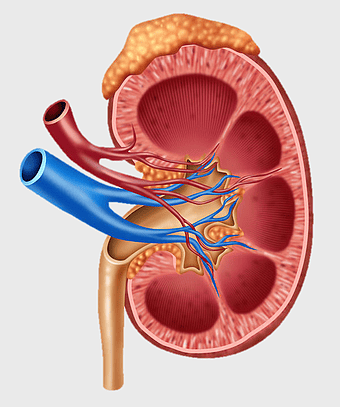

kidney anatomy, human kidney illustration, kidney cancer awareness, kidney organ diagram, renal system structure, medical kidney image, urinary system components -

chronic kidney disease illustration, nephron structure diagram, kidney transplant medical image, excretory system anatomy, renal blood flow visualization, human kidney cross-section, medical education graphics -

kidney anatomy diagram, human kidney structure, retroperitoneal space illustration, blood vessels in kidneys, renal system visualization, medical kidney illustration, kidney cross-section analysis -

kidney anatomy diagram, human kidney structure, adrenal gland and kidney, kidney stone illustration, renal system diagram, urinary system anatomy, kidney blood vessels -